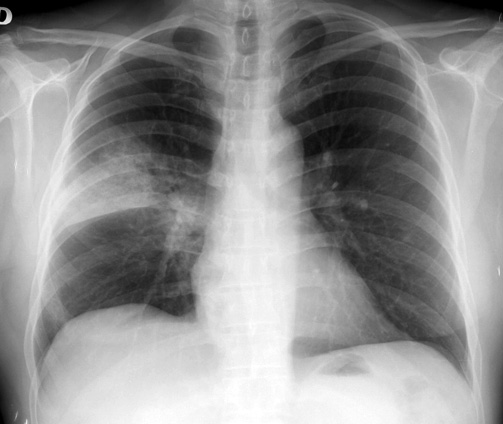

Neumonías adquiridas en la comunidad en pacientes con enfermedad pulmonar obstructiva crónica tratados con corticoides inhalados u otros broncodilatadores. Estudio PNEUMOCORT

Aten Primaria. 2018. No hubo diferencias entre cohortes en el riesgo de neumonía adquirida en la comunidad (NAC) ni exacerbaciones graves. Las exacerbaciones leves fueron superiores en el grupo corticoides inhalados (CI). Tanto NAC como exacerbaciones graves fueron más frecuentes en pacientes con EPOC grave y en pacientes tratados con dosis altas de CI.

Neumonía adquirida en la comunidad: actualización